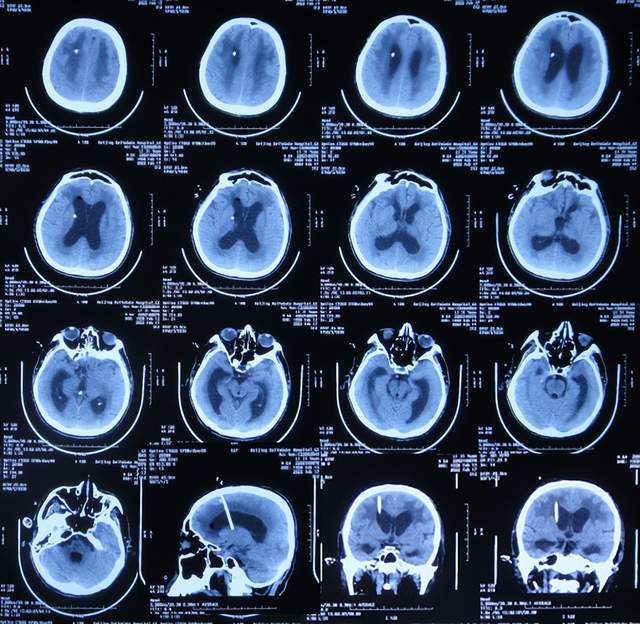

患者于2021年9月2日突发昏迷,急送至当地的山东省滨州市惠民县某医院,查头颅CT示脑出血破入脑室(图-1),急诊行双侧脑室外引流术;脑出血后血压偏低,给予输注入人血白蛋白。

图-1:2021年9月2日头颅CT

术后次日即2021年9月3日,患者意识转清醒,能简单言语,肢体可以遵嘱抬起;查头颅CT示双侧脑室引流术后,脑室积血(图-2)。

图-2:2021年9月3日头颅CT

双侧脑室外引流术后3天即2021年9月5日,查头颅CT示脑室内积血减少(图-3)。

图-3:2021年9月5日头颅CT

双侧脑室外引流术后6天即2021年9月8日,再次查头颅CT示仍有少量积血(图-4);给予常规拔除了双侧脑室外引流管,同时进行了腰大池引流术。

图-4:2021年9月8日头颅CT

腰大池引流术后4天即2021年9月12日,查头颅CT示脑室内积血基本消失(图-5)。

图-5:2021年9月12日头颅CT

拔除腰大池引流管后3天即2021年9月23日,查头颅CT示(图-6)后继续给予保守治疗。

图-6:2021年9月23日头颅CT

腰大池引流管拔除后13天即2021年10月3日,患者恢复至可以搀扶下行走约20米,能简单言语,查头颅CT较2021年9月23日认为没有明显变化(图-7)。

图-7:2021年10月3日头颅CT

但继续保留治疗20余天的时间内,患者逐渐出现意识变差,走路变差,至2021年11月3日(腰大池引流管拔除后31天),病情变重致不能走路,不能言语,查头颅CT(图-8)后考虑脑积水,给予腰椎穿刺治疗。

图-8:2021年11月3日头颅CT

但腰椎穿刺治疗7天病情无明显改善,于2021年11月10日(住院治疗2月余)出院回家休养,出院时头颅CT示仍有脑积水(图-9);出院时:意识差,不能走路,不能言语。

图-9:2021年11月10日头颅CT

出院1个半月后,因患者病情无改善,家属想做脑室腹腔分流术,于2021年12月22日前往上级的山东省滨州市某三甲医院就诊,查头颅CT示脑积水(图-10);但腰椎穿刺检查示颅内压低;胸部CT有肺部脓肿(片子丢失),暂时给予抗感染治疗。

图-10:2021年12月22日头颅CT

给予抗感染治疗个月后即2022年1月17日,肺部脓肿明显变小(片子丢失),查头颅CT仍脑积水(图-11),未给予脑室腹腔分流术,建议暂时回家休养,但患者意识仍不好,不能走路,不能说话,体型变消瘦。

图-11:2022年1月17日头颅CT

入院时查头颅CT示脑积水(图-13);肺部CT示肺部感染(图-14)。

图-13:2022年2月16日头颅CT

入院次日,给予脑室外引流术,查头颅CT示脑室外引流术后状态(图-15)。

图-15:2022年2月17日头颅CT

2022年3月1日(入院治疗13天),病情进一步改为:意识便完全正常,大小便变正常,扶着能坐起,言语交流变基本正常(图-17);头颅CT示脑室变小(图-18)。

图-18:2022年3月2日头颅CT

2022年4月7日(入院治疗50天),查头颅CT示脑室引流术后状态,未见异常(图-22)。

图-22:2022年4月7日头颅CT

2022年4月27日(入院治疗70天)家属要求出院回家休养。出院时:携带脑室腹壁外引流管;精神变得挺好,能自己站立但自己走路不稳,体重较入院时明显增加,入院时消瘦病态的体型已基本恢复正常状态(图-23);出院时头颅CT示脑室引流状态(图-24)。

图-24:出院时头颅CT

出院后4个月即2022年8月30日,为了做脑积水分流术,再次来到李小勇脑脊液科,入院时:精神状态良好,能自己走路了稍不稳(图-25);头颅CT示脑室引流术术后状态(图-26)。

图-26:2022年8月30日头颅CT

完善各项检查后于2022年9月15日,进行了脑室腹腔分流术(图-27)。

图-27:2022年9月15日头颅CT